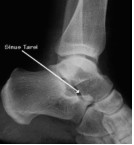

对于大多数人而言,崴脚仿佛是件很平常的事情。但是,其中不少人会发现:崴脚后,脚踝外侧还一直伴有疼痛。今天,就给大家介绍一个平时我们容易忽视的问题:跗骨窦综合征(sinus tarsi syndrome STS)

踝关节扭伤是最常见的运动损伤之一,有报道显示约70%的病人在急性期过后仍感觉持续疼痛,甚至迁延不愈。此时,我们在排除其他可能的病理因素,如慢性踝关节不稳,踝关节内骨性或软组织撞击、跗骨联合等后,大部分病人可诊断为跗骨窦综合征。目前认为这是距下关节周围病变的一种复合性疾病,与距下关节的轻微不稳定、韧带损伤、关节纤维化、关节去神经改变或窦内压增高等改变有关。

辅助检查:核磁共振MRI必不可少,它可以观察到一些病理改变包括纤维化,弥漫性浸润,非特异性炎症改变,以及异常积液。并发现这些改变与外侧副韧带撕裂之间的相互关系。